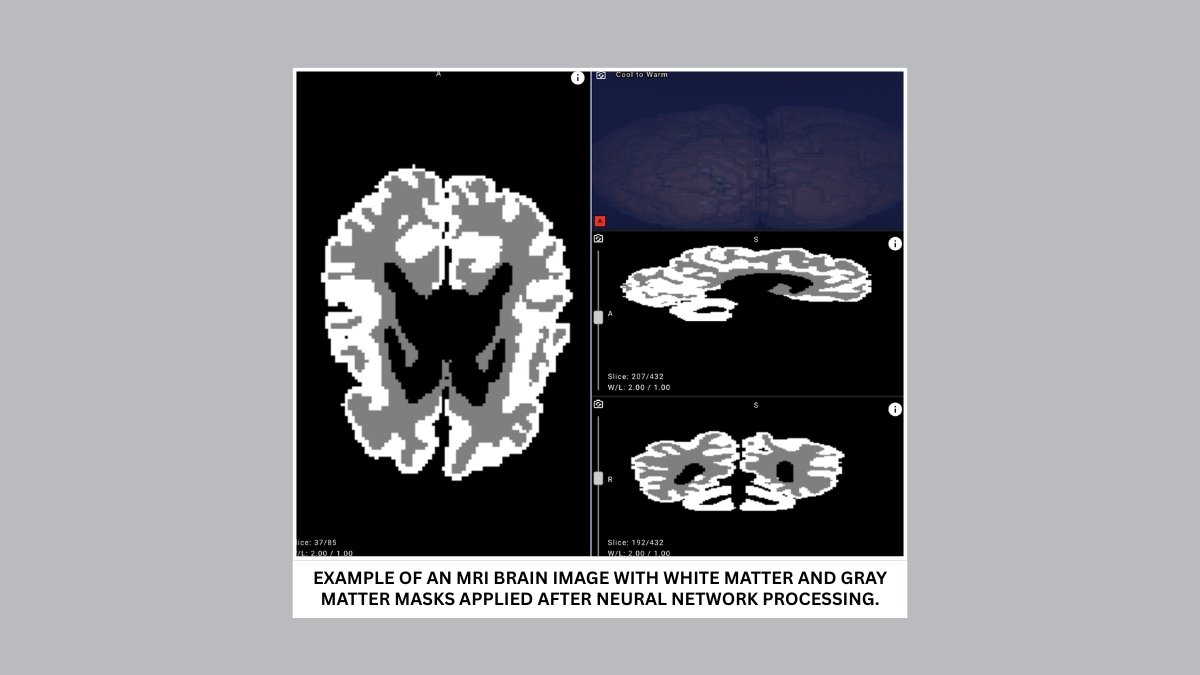

The proposed solution analyzes MRI scans and can distinguish between gray and white brain matter with over 90% accuracy. Cutting evaluation time from days to minutes, it enables earlier detection and more effective rehabilitation planning for infants with cerebral palsy and other central nervous system disorders.

Early diagnosis is critical for improving outcomes and ensuring effective rehabilitation. Yet detecting cerebral palsy within the first 12 months of life remains one of the most difficult tasks in modern medicine. An infant’s brain develops at a remarkable speed, and traditional MRI scans are difficult to interpret due to the low contrast between gray and white matter — the tissues that form the cerebral cortex and support higher brain functions.

To bridge this gap, Yandex researchers collaborated with medical experts to create new annotations, design a dedicated neural network architecture, and run a series of machine learning experiments. The resulting model achieved over 90% accuracy in distinguishing gray and white matter in infant brains on internal evaluation data, demonstrating its potential for clinical use.

- Improve accuracy and objectivity. With over 90% accuracy, the model highlights outlines and quantifies the ratio of gray to white matter in an infant’s brain.